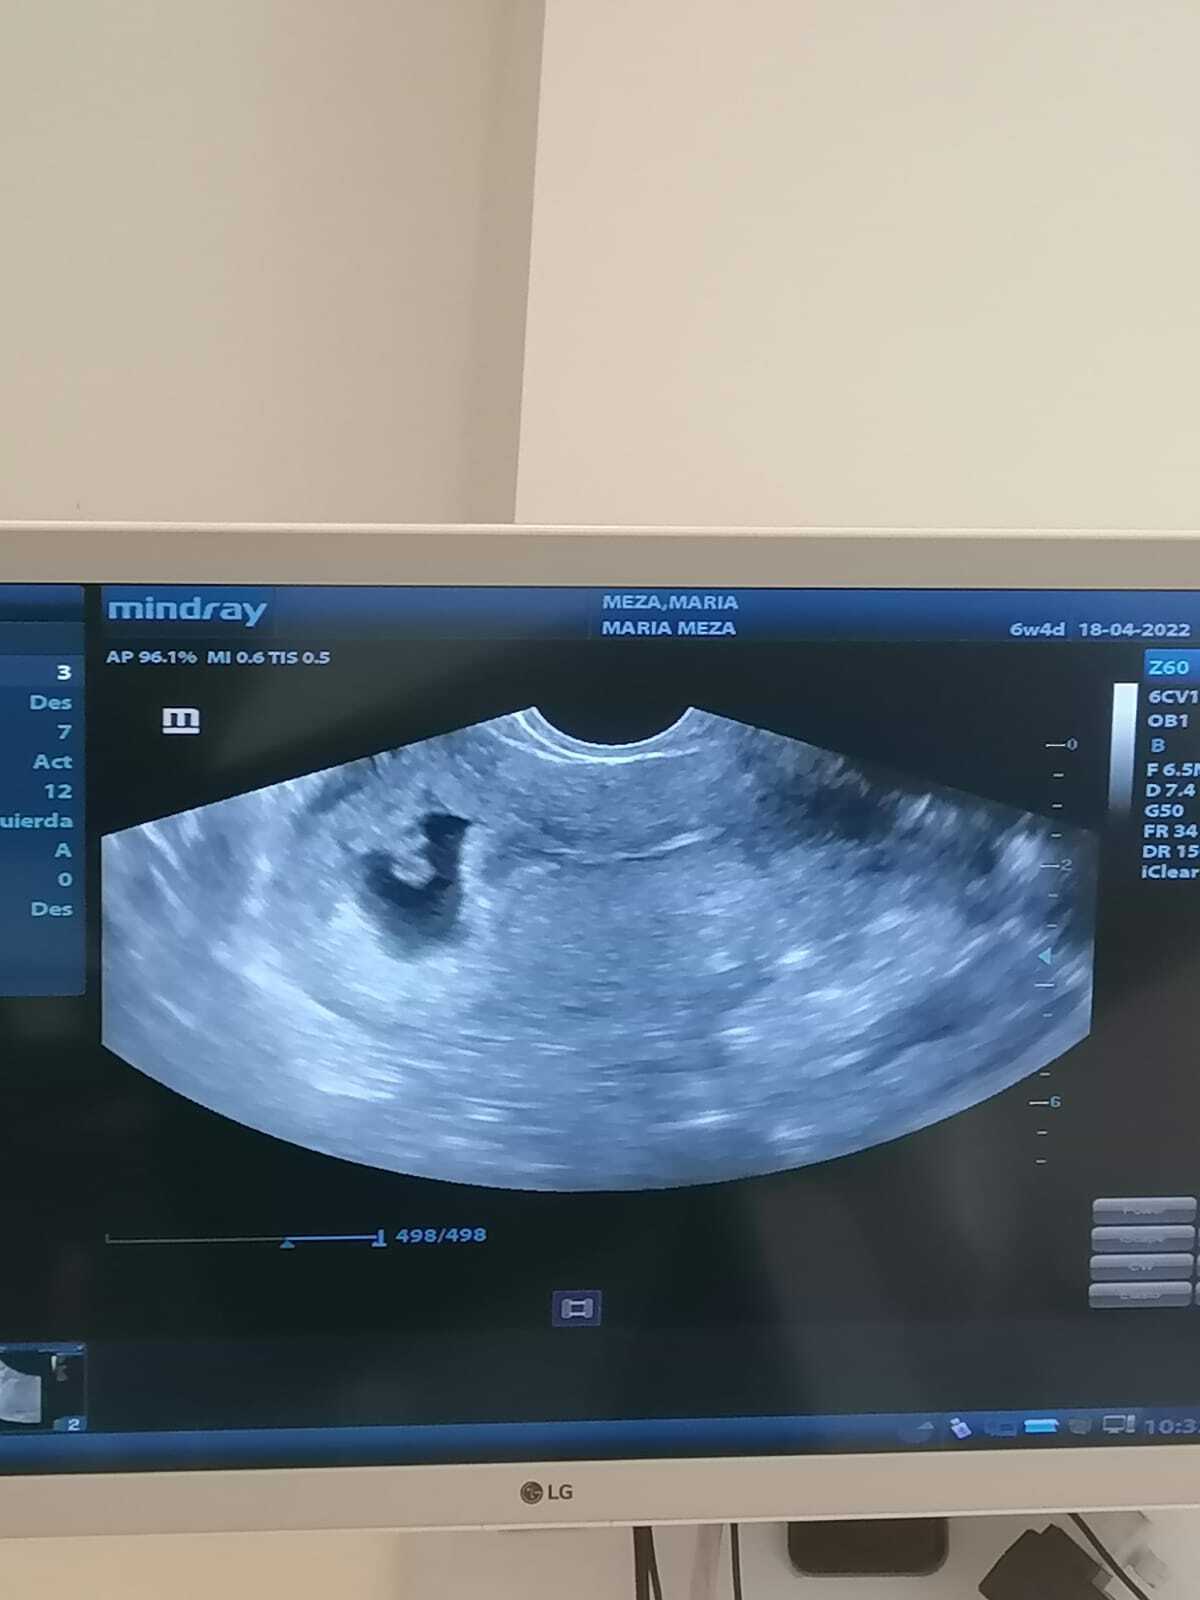

ULTRASON